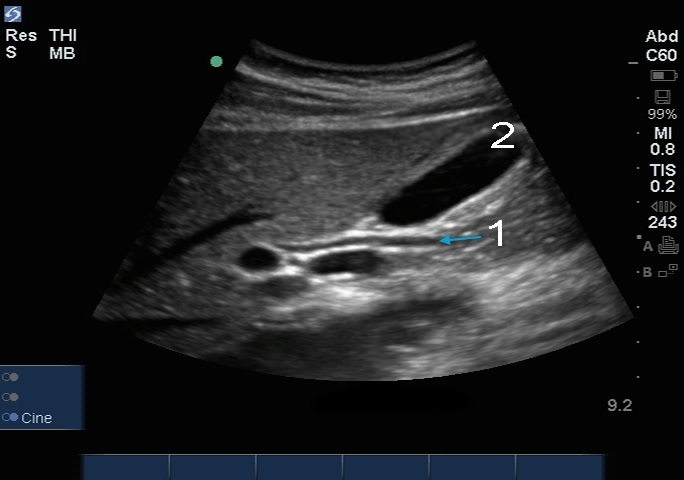

胆总管 (CBD)

胆囊 (GB)